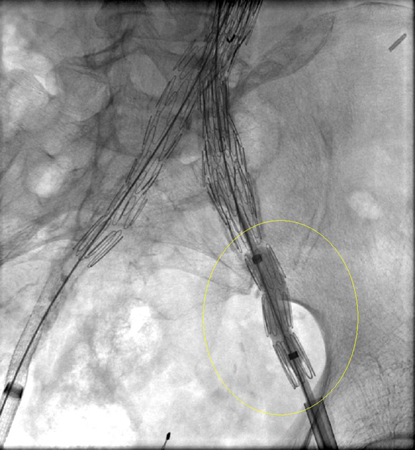

Deve-se fazer todo o esforço possível para reparar vazamentos (endoleaks) do tipo I antes de finalizar o procedimento (por exemplo, moldagem por balão da zona de vedação proximal, colocação de um manguito proximal, grampeamento interno, embolização líquida).[248] Para os pacientes com comprometimento da selagem proximal após um reparo endovascular do aneurisma da aorta abdominal, deve-se considerar uma extensão proximal com dispositivos fenestrados e ramificados.[2] Um endoleak do tipo IA persistente pode necessitar de conversão para reparo aberto, desde que o risco cirúrgico seja aceitável.[2][77][249][Figure caption and citation for the preceding image starts]: Enxerto de endoprótese de extensão implantado para o mesmo vazamento (endoleak) do tipo I (circulado)University of Michigan, mais especificamente os casos do Dr. Upchurch, representando os Departamentos de Cirurgia vascular e Radiologia [Citation ends].